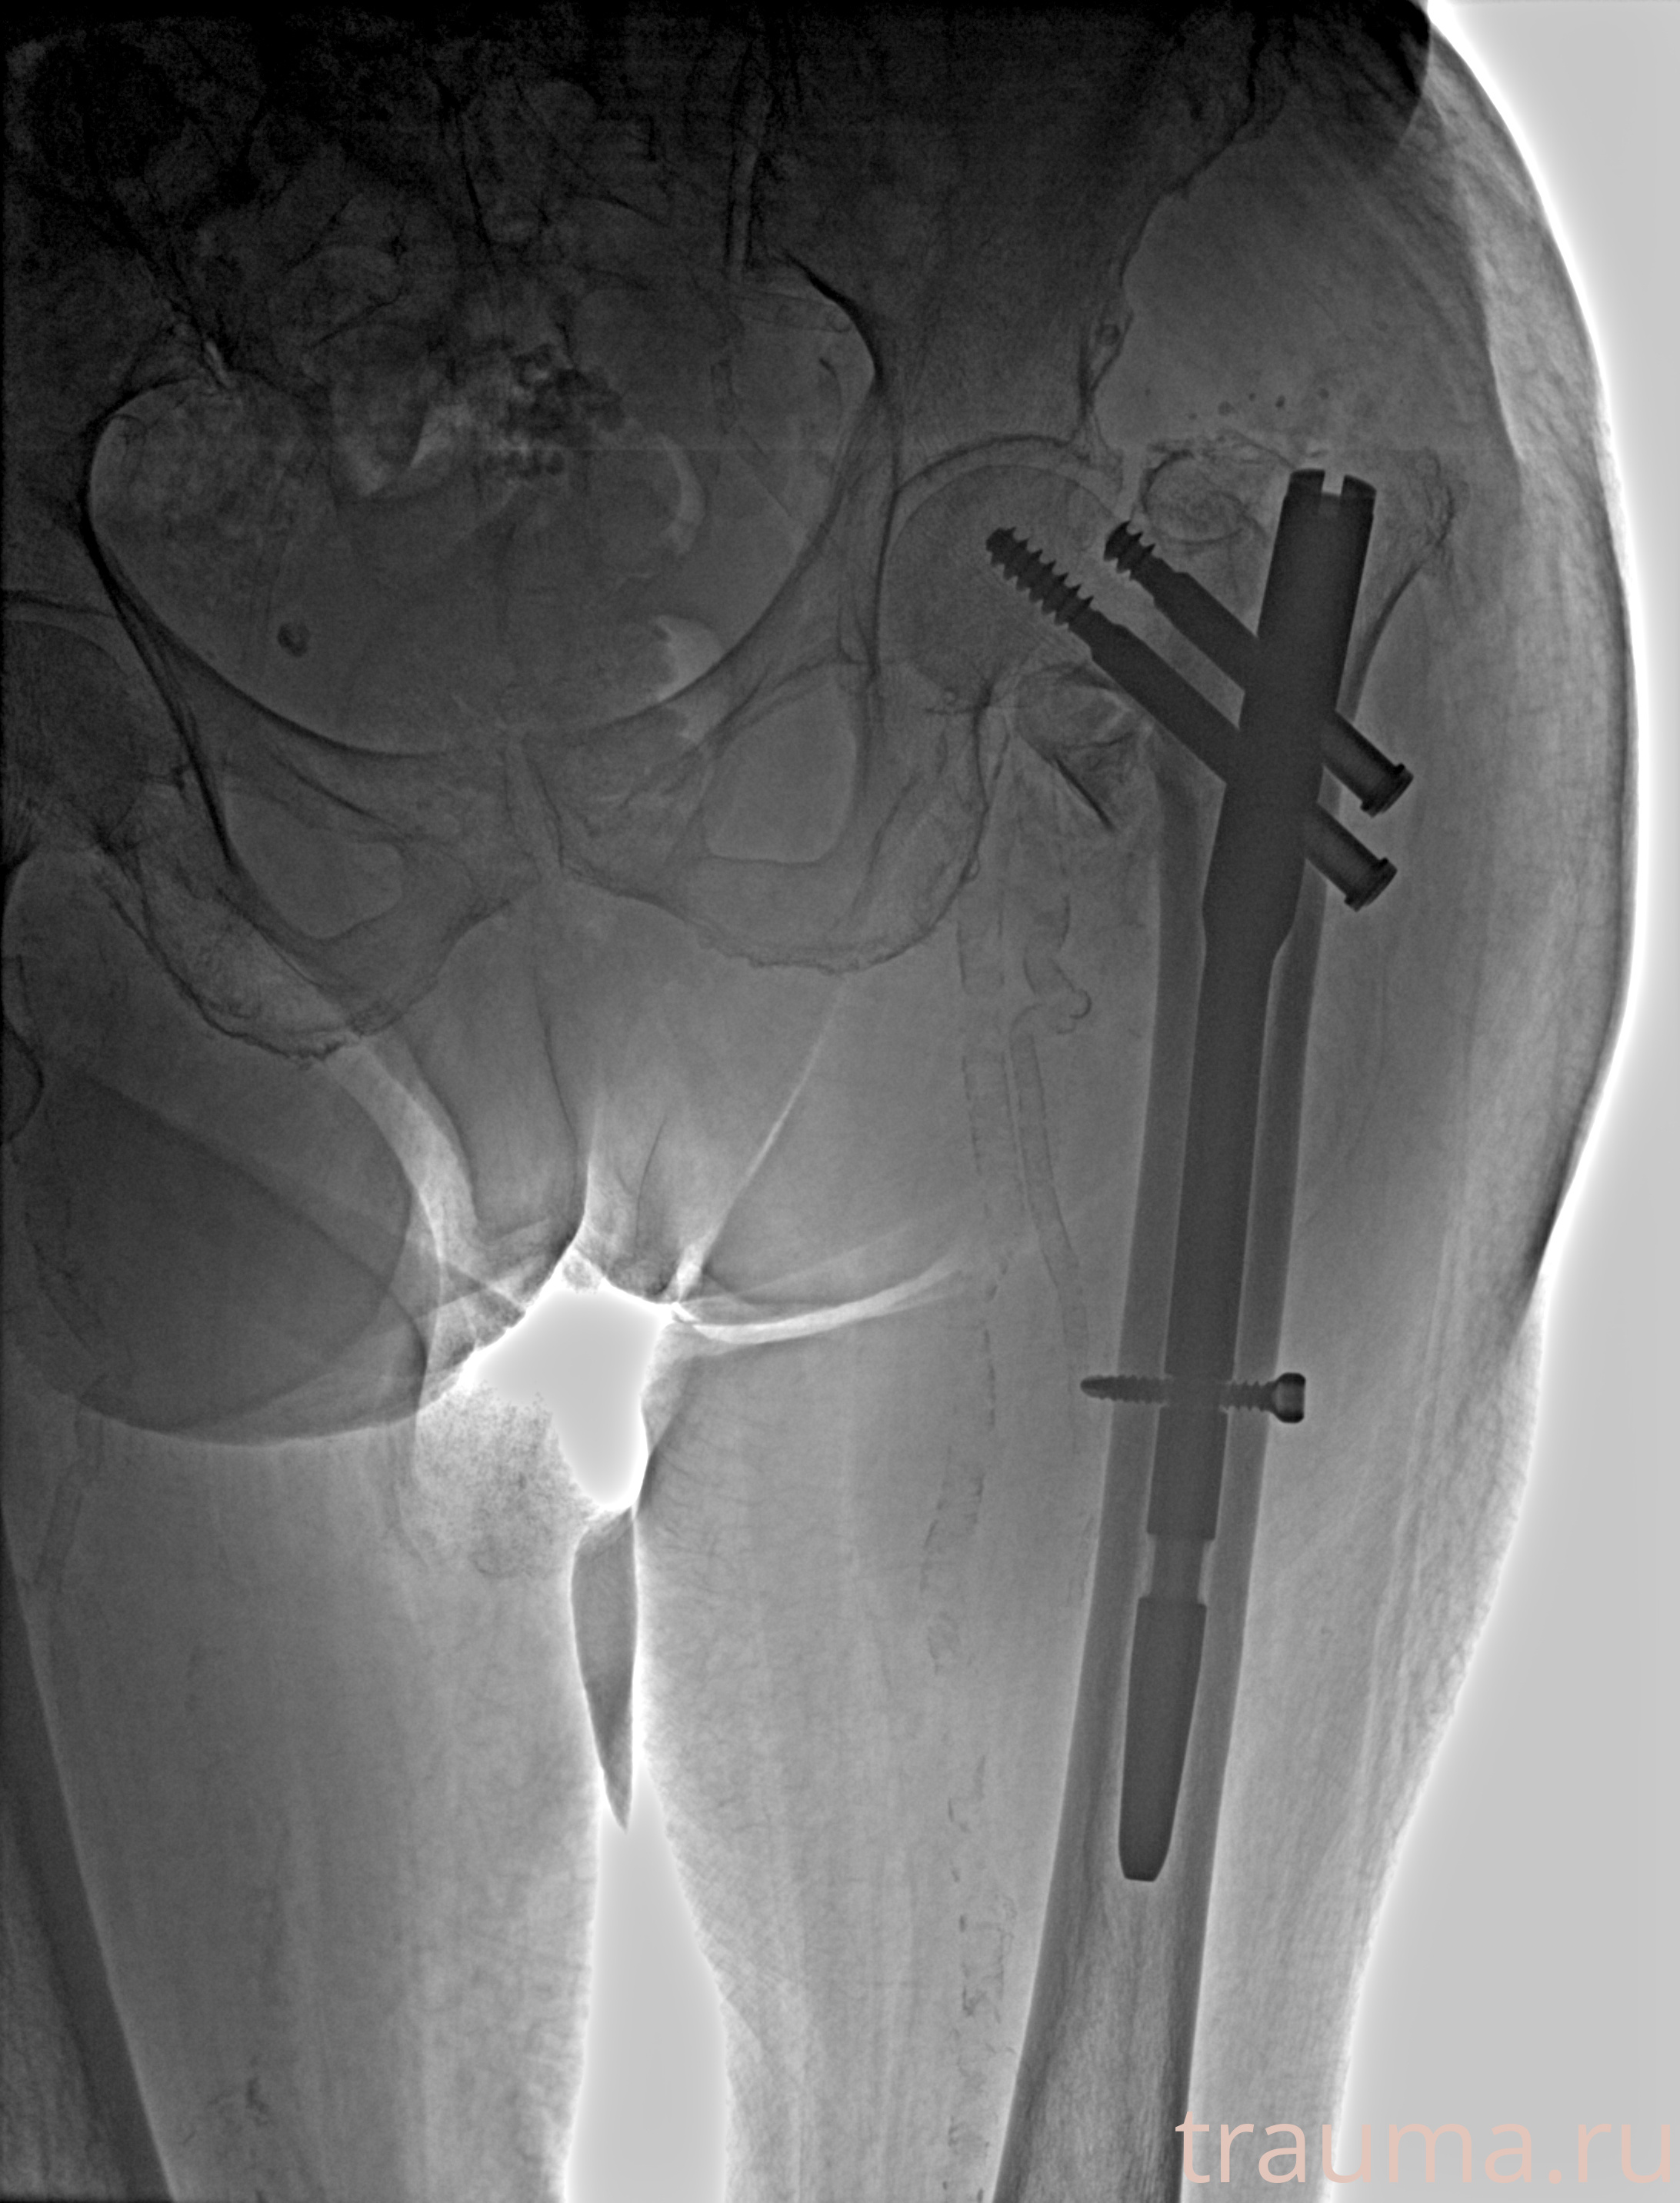

Рентгенограммы

Рентген на дому: по вашему адресу приезжает врач-рентгенолог, травматолог-ортопед с мобильным рентгеновским аппаратом, проводит диагностику травмы или заболевания, делает необходимые рентгенограммы, дает рекомендации по дальнейшему лечению. Получить качественные снимки в домашних условиях возможно благодаря уникальной методике, разработанной МосРентген Центром для института  Склифосовского